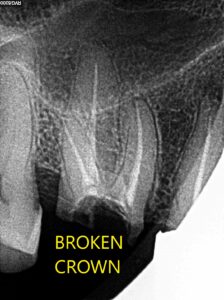

Successful case gallary